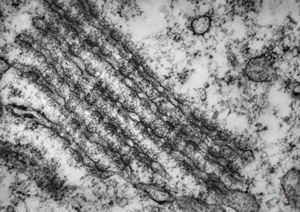

M,41y. | ribosome-lamella complex in tricholeukocyte -hairy cell leukemia, spleen

M,41y. | ribosome-lamella complex in tricholeukocyte -hairy cell leukemia, spleen

M,41y. | ribosome-lamella complex in tricholeukocyte -hairy cell leukemia, spleen